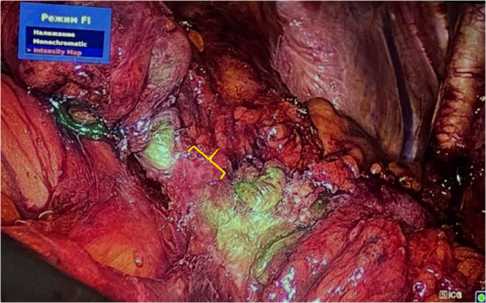

После обработки операционного поля и нефростомических дренажей в положении пациента лёжа на спине и установки уретрального катетера Ch 14 в стерильных условиях, пациент был переведён в положение Тренделенбурга. Далее осуществлён стандартный лапароскопический доступ в область малого таза с использованием оптического троакара в околопупочной области (10 мм), двух портов хирурга в левой подвздошной области (12 и 5 мм) и одного ассистентского порта в правой подвздошной области (5 мм). Нами была использована видеоэндоскопическая система с поддержкой флуоресцентной визуализации в режиме реального времени. Первым этапом операции тупым и острым способов была выполнена мобилизация зон обоих уретероилеальных анастомозов. При визуализации невооружённым глазом были выявлены участки уплотнения мочеточников в области уретероилеоанастомозов на протяжении 3 и 5 см слева и справа соответственно. Вторым этапом проведена ICG ангиография мочеточников. Анестезиологом была выполнена внутривенная инъекция готового раствора ICG-красителя (2 мг/мл) в объёме 5 мл. В течение полутора минут при активированном режиме флуоресценции краситель определялся в тканях мочеточников с достаточной перфузией в виде зелёного свечения с пиком концентрации через 4-5 мин. При повторной оценке кровоснабжения УИА определялись зоны отсутствия перфузии на протяжении 1 см слева и 2 см справа (рис. 2, 3).

Рис. 2. ICG-ангиография правого УИА: желтым выделена область стриктуры

Fig. 2. ICG-angiography of the right UIA: the area of stricture is highlighted in yellow

Рис. 3. ICG-ангиография правого УИА в монохромном режиме: желтым выделена область стриктуры

Fig. 3. ICG angiography of the right UIA: the area of stricture is highlighted in yellow